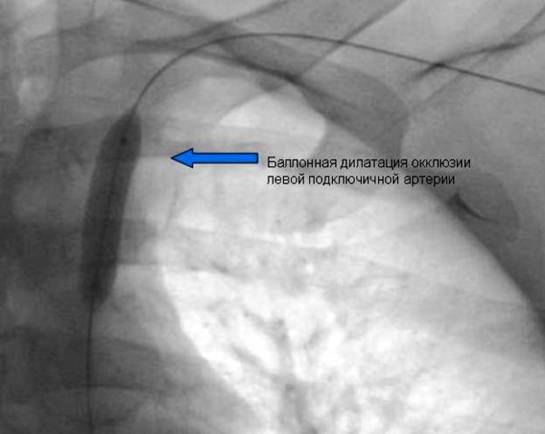

Окончатильный вид

Проходимость сосуда восстановлена полностью